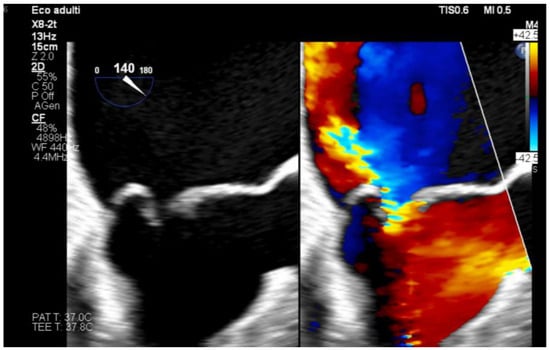

Anesthetic Management of Eosinophilic Granulomatosis with Polyangiitis: A Narrative Review with an Illustrative Case in Cardiac Surgery

by Debora Emanuela Torre and Carmelo Pirri

Background: Eosinophilic granulomatosis with polyangiitis (EGPA), formerly Churg–Strauss syndrome, is a rare necrotizing vasculitis characterized by asthma, eosinophilia, and systemic granulomatosis vasculitis. Perioperative risk is primarily driven by airway hyperreactivity, potential cardiac disease, chronic immunosuppressive therapy, and reported alterations in plasma cholinesterase [...] Read more.

Background: Eosinophilic granulomatosis with polyangiitis (EGPA), formerly Churg–Strauss syndrome, is a rare necrotizing vasculitis characterized by asthma, eosinophilia, and systemic granulomatosis vasculitis. Perioperative risk is primarily driven by airway hyperreactivity, potential cardiac disease, chronic immunosuppressive therapy, and reported alterations in plasma cholinesterase activity. Evidence specifically addressing anesthetic management remains scarce and largely limited to case-based reports. Methods: A focused narrative review was conducted by searching MEDLINE (via PubMed), Scopus, and Embase from inception to January 2026 for publications reporting perioperative anesthetic management in patients with EGPA/Churg–Strauss syndrome. Case reports and case-based descriptions providing explicit anesthetic details were qualitatively synthesized. Results: Available evidence consists predominantly of isolated case reports across heterogeneous surgical settings, including ENT, abdominal, orthopedic, ambulatory, pediatric, and rare cardiac procedures. Recurring perioperative principles include optimization of bronchial disease and continuation of inhaled therapy; minimization of airway stimulation and avoidance of histamine-releasing drugs; selection of induction agents preserving hemodynamic stability in the presence of myocardial involvement; preference for non-depolarizing neuromuscular blockade with quantitative monitoring (and consideration for sugammadex when appropriate); individualized corticosteroid management and multimodal, opioid-sparing analgesia, often supported by regional techniques. Conclusions: In the absence of dedicated perioperative guidelines, anesthetic care for EGPA should be individualized based on clinical phenotype and organ involvement. A structured approach targeting airway protection, cardiovascular stability, safe neuromuscular management, and opioid-sparing analgesia may represent a pragmatic risk-mitigation framework. These considerations are illustrated by an institutional experience in mitral valve surgery. Full article

Show Figures

Figure 1